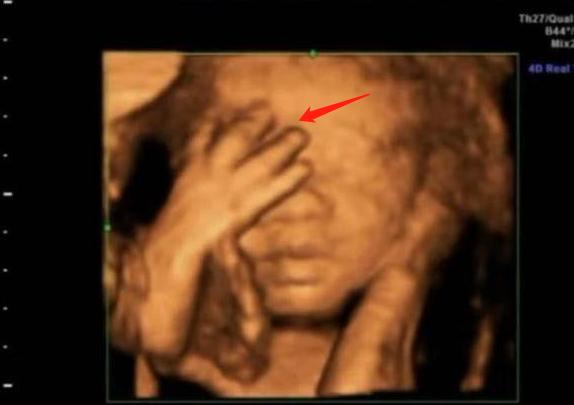

3.“捂鼻胎儿”火了,孕妈做四维彩超遭医生怒斥:真无知

前段时间,30岁的准妈咪小青去医院做四维胎超,当医生看到屏幕画面后,眉头紧锁,她们无法解释胎儿为何会做出如此奇怪的动作。

画面中,胎儿双手捂着鼻子,脸部表情十分痛苦,好似在与某种看不见的东西做抗争。